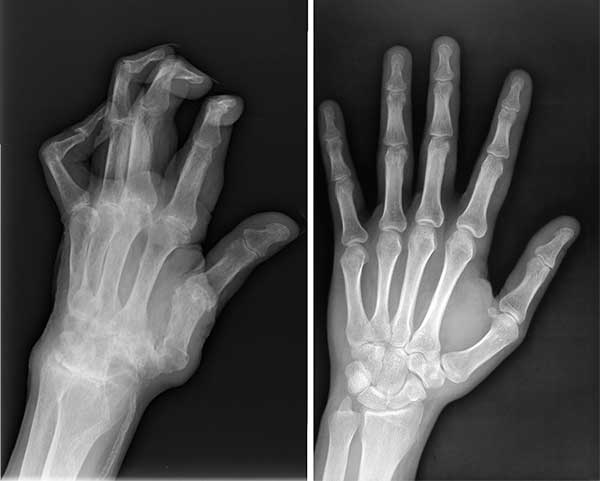

Saya bukan satu-satunya yang diselamatkan oleh produk ajaib ini. Suami saya menderita sakit di lengannya untuk waktu yang lama. Jari-jarinya mengalami cedera parah, dan kemudian didiagnosis menderita radang sendi. Saya memutuskan membeli Invanil untuk dia. Kami minum bubuk ini bersama-sama dan produknya berhasil menyembuhkan kita berdua.

Rontgen suami sebelum dan sesudah mengonsumsi Invanil

Keadaan tangan suami saya sebelum dan sesudah mengonsumsi Invanil